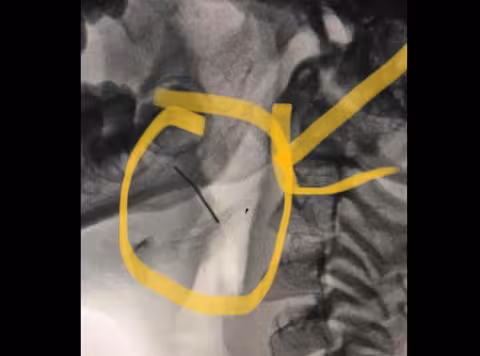

Семирічна дівчинка з Дрогобича потрапила до нас за скеруванням від районного ЛОРа. Нашому завідувачу ЛОР-відділення Федору Юрочку передали рентген-знімки дитини. Сумнівів не було — у горлі дитини чітко видно стороннє тіло.

»Наші анестезіологи виконали дитині наркоз за особливою методикою, який дозволяє оперувати без застосування ендотрахеальної трубки. У такий спосіб діставати сторонній предмет з горла набагато легше. Працювали ендоскопом. При дуже ретельному огляді ми побачили у тканині кореня язикового мигдалика дротик. Видно, мама пробувала його дістати, але її зусилля дали зворотній ефект — дротик зайшов ще глибше у тканини. Нам вдалося забрати його щипцями, обійшлися без розтинів тканин. Довжина його — приблизно 2 сантиметри", — розповів Федір Юрочко.